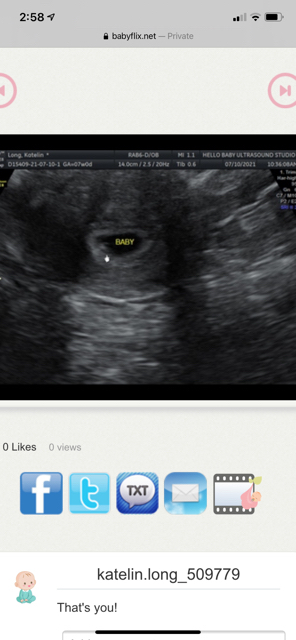

Based off ramzi theory what am I having? This is 7 week abdominal ultrasound